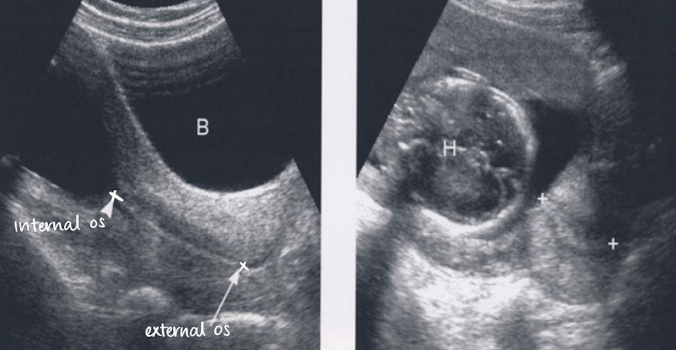

is this normal or cervical incompetence?

normal

incompetence